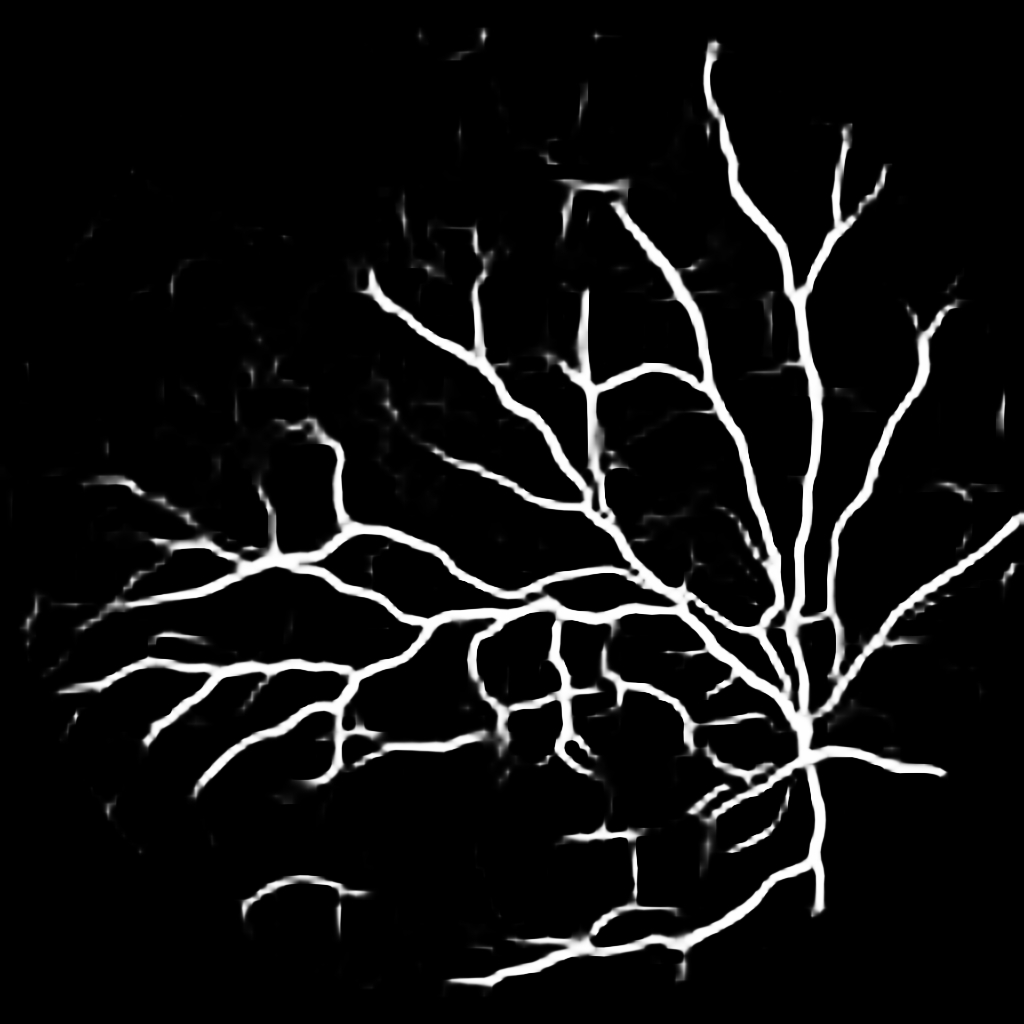

For completeness, and to test the robustness of our method, the models were also tested with several images sourced from Google™. We purposefully sourced extremely poor quality images (i.e. images with low contrast, speckle artefacts, etc), as well as images of pathological cases (i.e. Exdudates, Hemorrhages, etc). As there are no ground truth labels, only a qualitative assessment can be made of the results shown in Figure 2. In all cases, the models have accurately segmented the vessel structure whilst ignoring imaging artifacts and pathological lesions. This is very evident in the case of (5) and (6) where no vessels were segmented in areas of severe hemorrhaging.

{L to R: (1) Healthy, (2) Unhealthy, (3) Speckle Artefacts, (4) NPDR, (5) PDR, (6) Hemorrhages}